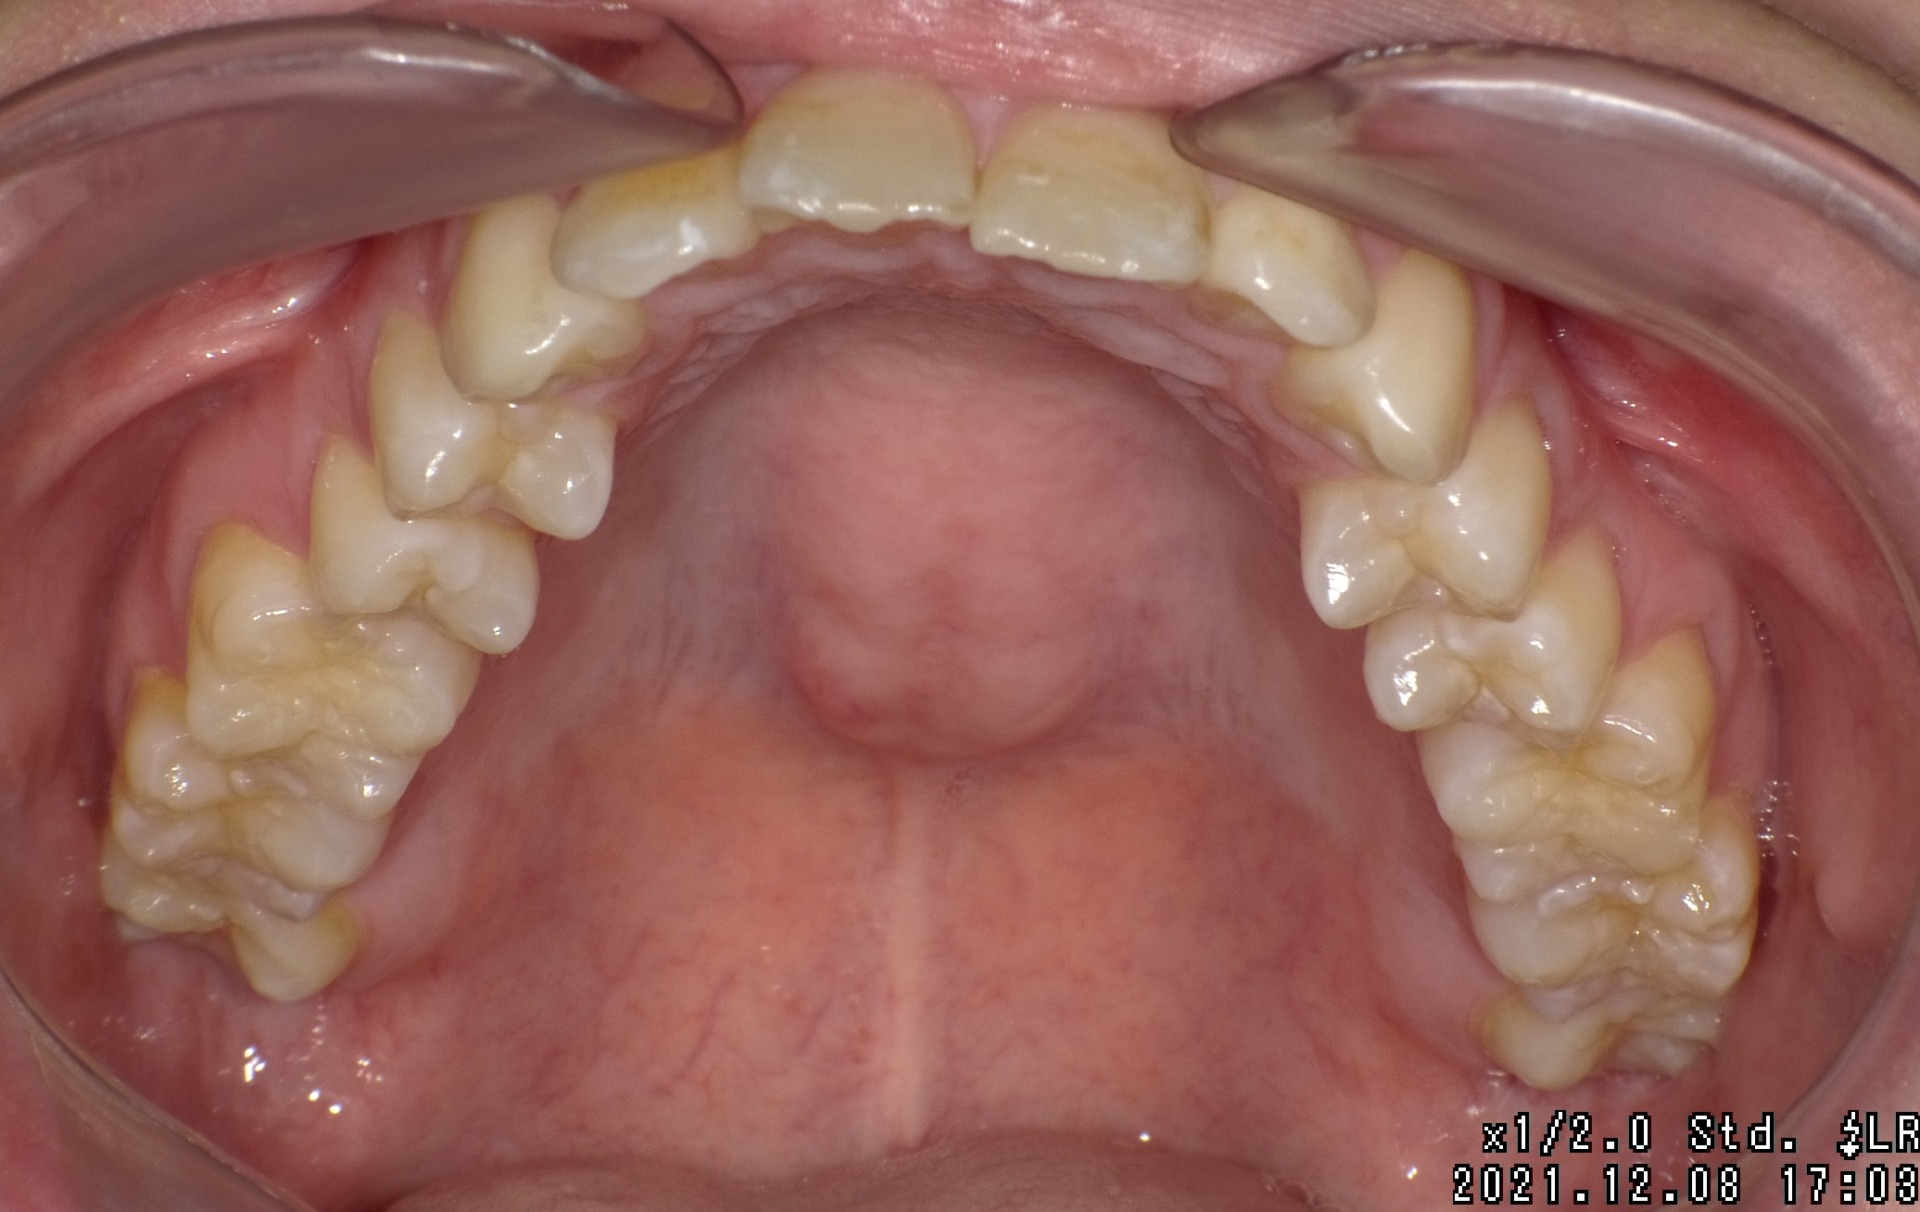

Before